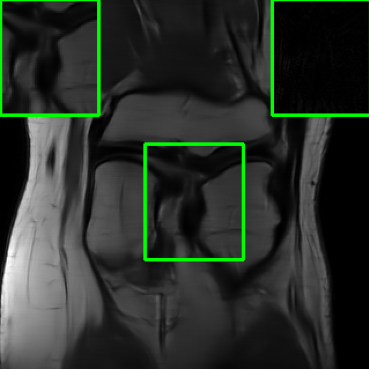

| Ground Truth | Vanilla MoDL | RS-E2E | SMUG |

![]() |

| PSNR = dB | PSNR = 24.84 dB | PSNR = 25.78 dB | PSNR = 30.81 dB |

| AT | Score-MRI | Deep-Equilibrium | Weighted-SMUG |

| PSNR = 30.72 dB | PSNR = 30.21 dB | PSNR = 24.58 dB | PSNR = 31.41 dB |

Results for the FastMRI Brain Dataset: we present the robustness results of the proposed approaches w.r.t. additive noise. In particular, the evaluation is conducted on the clean, noisy (with added Gaussian noise), and worst-case perturbed (using PGD for each method) measurements. Fig. 3 presents testing set PSNR and SSIM values as box plots for different smoothing architectures, along with vanilla MoDL and the other baselines using the brain dataset. The clean accuracies of Weighted SMUG and SMUG are similar to vanilla MoDL indicating a good clean accuracy vs. robustness trade-off. As indicated by the PSNR and SSIM values, we observe that weighted SMUG, on average, outperforms all other baselines in robust accuracy (the second and third set of box plots of the two rows in Fig. 3). This observation is consistent with the visualization of reconstructed images for the brain dataset in Fig. 4. We note that weighted SMUG requires longer time for training, which represents a trade-off. When comparing to AT, we observe that AT is comparable to SMUG in the case of robust (or worst-case noise) accuracy. However, the drop in clean accuracy (without perturbations) for AT is significantly larger than for SMUG. Furthermore, AT takes a much longer training time as it requires to solve an optimization problem (PGD) for every training data sample at every iteration to obtain the worst-case perturbations. Furthermore, we observe that its effectiveness is degraded for other perturbations including random noise as well as modified sampling rates shown in the next subsection. Importantly, the proposed SMUG and Weighted SMUG are not trained to be robust to any specific perturbations or instabilities, but are nevertheless effective for several scenarios.